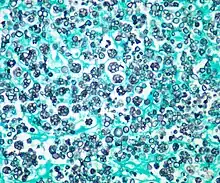

| Histologic stain of a Prototheca zopfii infection in a dog | |

Protothecosis, otherwise known as Algaemia, is a disease found in dogs, cats, cattle, and humans caused by a type of green alga known as Prototheca that lacks chlorophyll and enters the human or animal bloodstream. It and its close relative Helicosporidium are unusual in that they are actually green algae that have become parasites.[1] The two most common species are Prototheca wickerhamii and Prototheca zopfii. Both are known to cause disease in dogs, while most human cases are caused by P. wickerhami.[2] Prototheca is found worldwide in sewage and soil. Infection is rare despite high exposure, and can be related to a defective immune system.[3] In dogs, females and Collies are most commonly affected.[4]

Prototheca has been thought to be a mutant of Chlorella, a type of single-celled green alga. However, while Chlorella contains galactose and galactosamine in the cell wall, Prototheca lacks these. Also, Chlorella obtains its energy through photosynthesis, while Prototheca is saprotrophic, feeding on dead and decaying organic matter. When Prototheca was first isolated from slime flux of trees in 1894, it was thought to be a type of fungus.[6] Its size varies from 2 to 15 micrometres.[7]